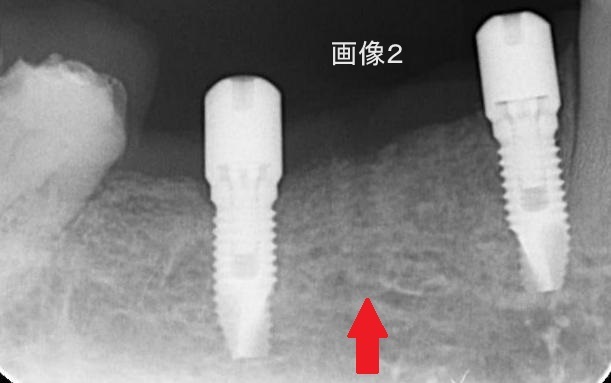

画像2

2つのインプラントが骨としっかり結合したことが確認できたら

撤去します。(赤い矢印)